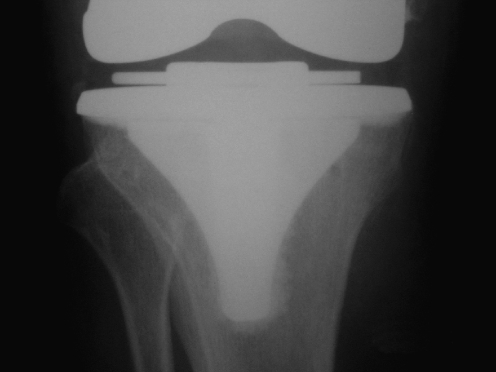

All of the X-rays were assessed for RLLs by two of the authors independently at different times. The X-rays were blinded for the single-stage versus the two-stage cementing techniques. Although radiolucency has been previously defined as a radiolucent zone of any size between the cement and bone [2], we observed radiolucencies in the implant-cement interface as well on both the AP and Lat radiographs. The width was measured in millimetres. In condylar designs, a radiolucent zone is more frequent around the tibial than the femoral component [3]. Thus, in this study we only measured the RLLs under the tibial tray. The Knee Society Roentgenographic Evaluation system of Ewald [6] and Modified Radiographic Evaluation System of Bach et al. [2] were used to determine and assess the RLLs. In the AP view (Fig. 1a), the radiolucent zones under the tibial tray were delineated in zones 1 and 2 (medial) and 3 and 4 (lateral). The radiolucent zones 5, 6 and 7 represented the keel area. In the Lat view (Fig. 1b), radiolucent zone 1 is anterior, zone 2 is posterior and zone 3 is at the tip of the keel. We measured the RLLs present in each of the specific component zones [6] as well as the sum of the width of RLLs measured on combined AP and Lat views [2]. If the total sum of the widths of the RLLs was 4 mm or less, the category ‘narrow’ was used; if the total sum of the widths was greater than 4 mm, the category ‘wide’ was used [2].

Fig. 1.

Anterior-posterior (AP) (a) and lateral (Lat) (b) views of a representative tibial component showing the zones for the radiolucent lines (RLLs). The depth of the RLLs is measured in millimetres